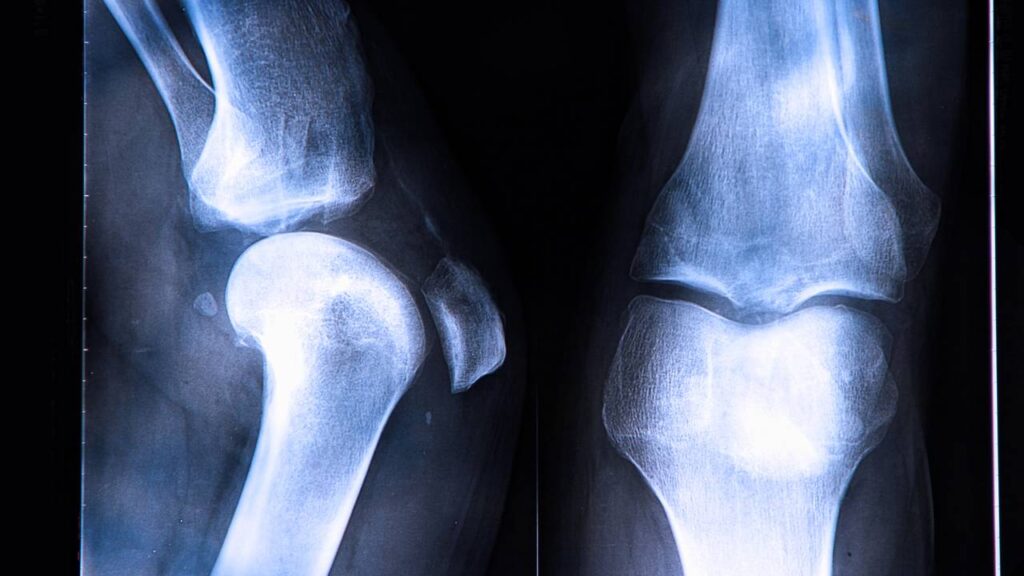

A chamada lesão no ligamento cruzado anterior em jogador de futebol está entre os problemas de joelho mais estudados na medicina esportiva. O LCA é um dos principais ligamentos internos do joelho e funciona como um “freio” para movimentos bruscos de translação e rotação da tíbia em relação ao fêmur.

Em lances comuns de jogo, como mudança rápida de direção, aterrissagem de um salto ou disputa de bola em velocidade, a estrutura pode ser submetida a forças além do limite de resistência. Sem o LCA íntegro, o joelho tende a ficar instável, dando a impressão de “falseio” e prejudicando gestos como arranques, desacelerações e mudanças de direção.

Além do ligamento, a lesão no menisco lateral também chama atenção no caso do atacante brasileiro. O menisco é uma estrutura de fibrocartilagem em forma de “meia-lua”, localizada entre o fêmur e a tíbia, e o menisco lateral ocupa a parte externa da articulação do joelho.

No joelho direito de Rodrygo, a parte atingida foi justamente o menisco lateral, que funciona como uma espécie de amortecedor, distribuindo a carga durante a corrida, o chute e os giros típicos do futebol. Quando ele é danificado, aumenta a sobrecarga sobre a cartilagem e o risco de desgaste precoce a médio e longo prazo.